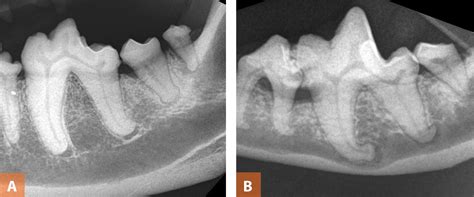

Interpretation Of Dental Radiographs In Dogs And Cats, Part 2: Normal

Interpretation of Dental Radiographs in Dogs and Cats, Part 2: Normal todaysveterinarypractice.com

dental radiographs dogs abnormal normal cats tooth teeth root molar roots veterinary interpretation fused premolar mandibular imaging variations findings anatomic